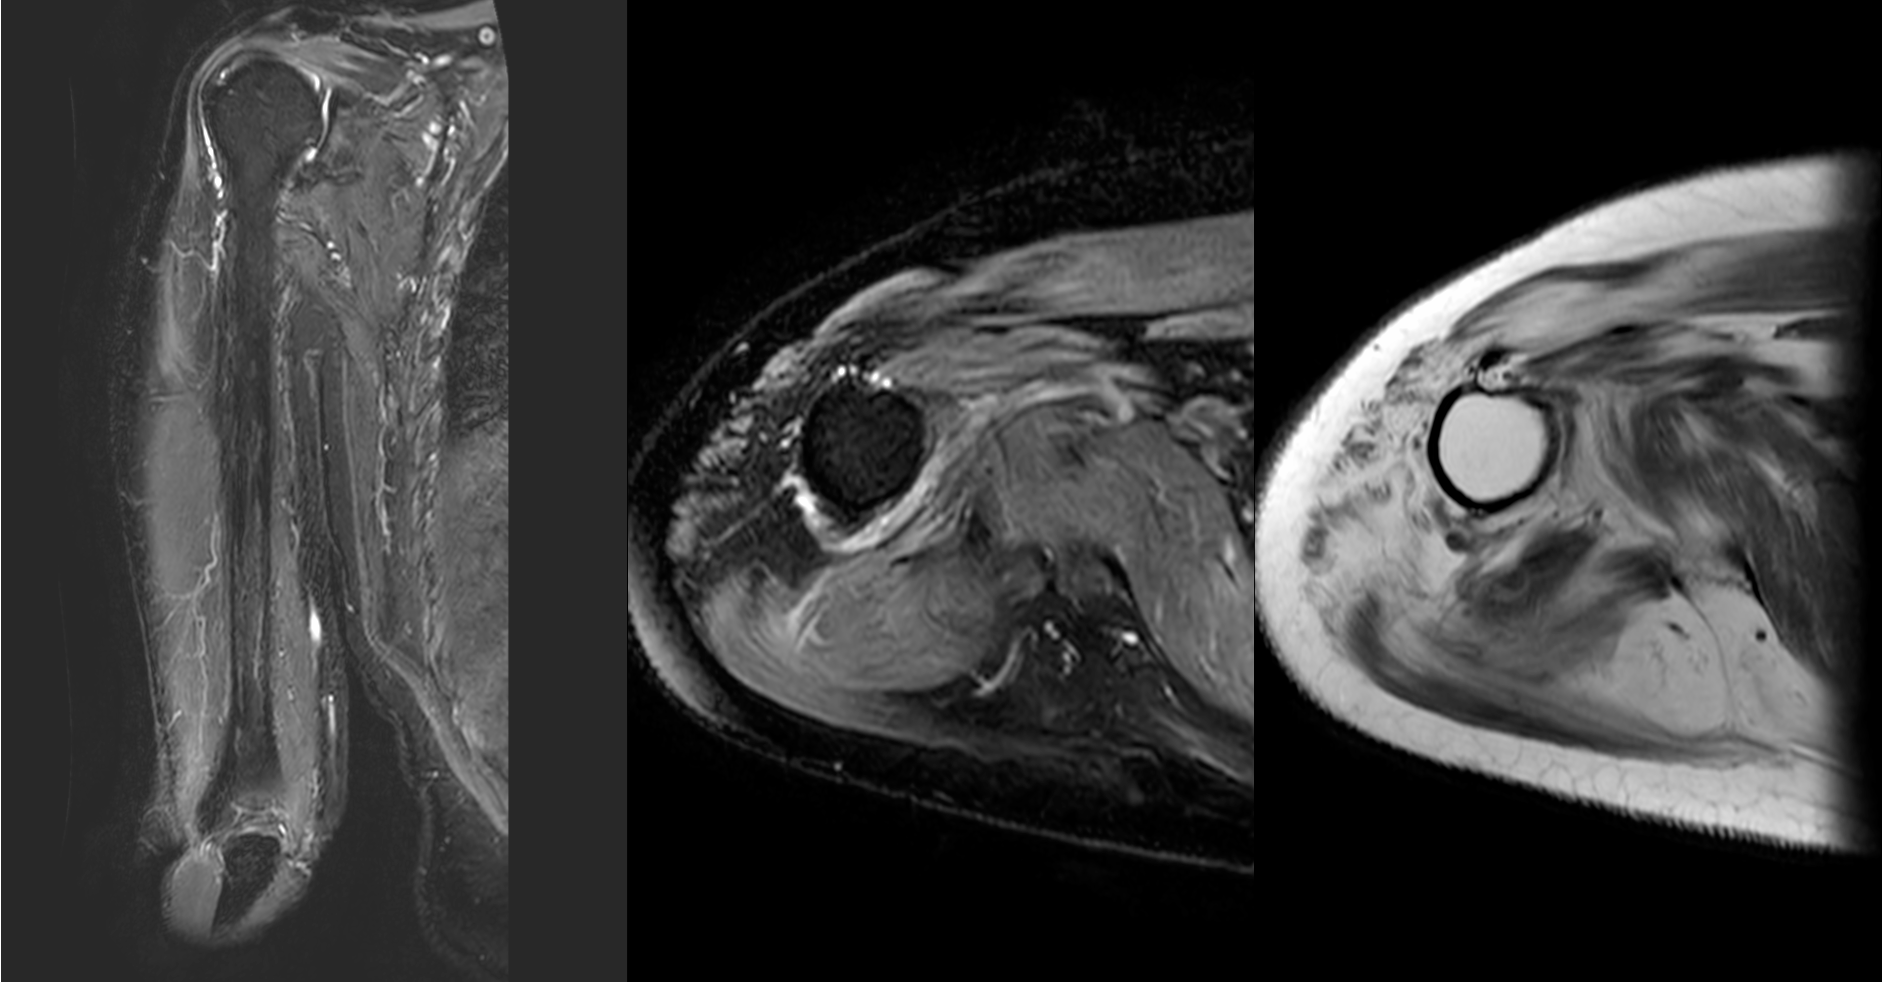

Case 61: Dermatomyositis and the Myositis Protocol MRI

55-years old with dermatomyositis

55-years old diagnosed to have dermatomyositis, referred for a myositis protocol MRI.